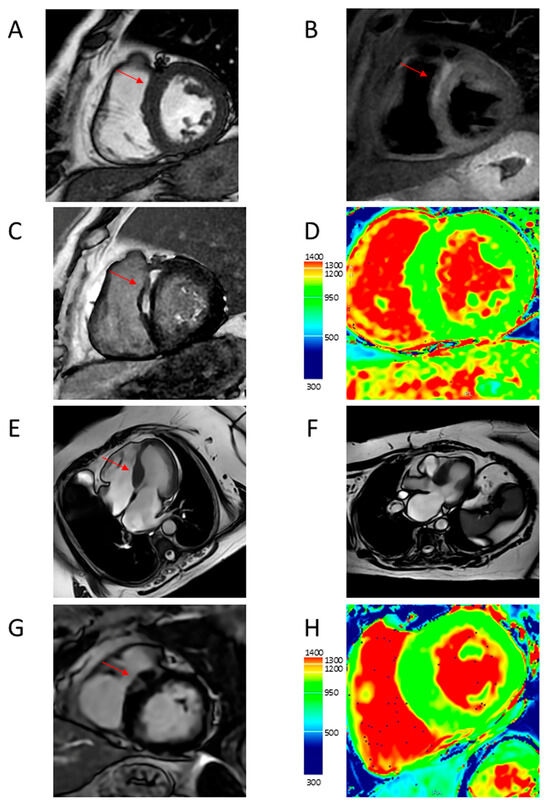

4.5. Myocardial Fibrosis

4.6. Microvascular Dysfunction

5.2. Characterization of HCM Phenotypes and Risk Stratification